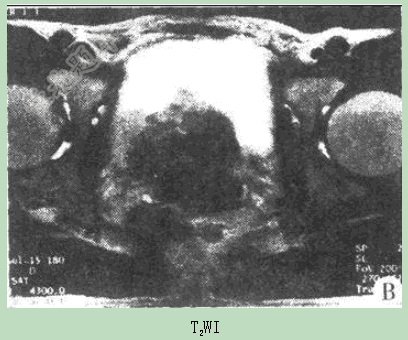

- 单项选择题患者男性,74岁,进行性排尿困难4月,MR图像如下,最有可能的诊断是( )。

D、前列腺癌